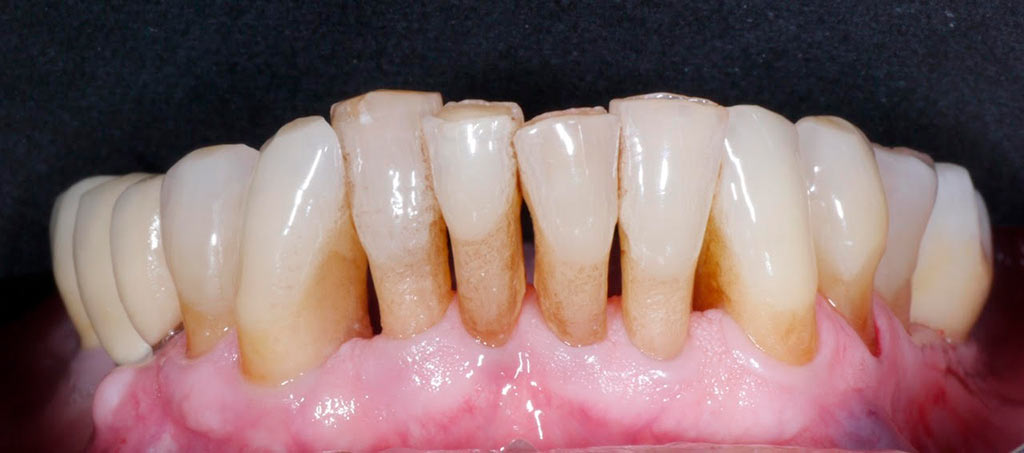

Rehabilitacion de paciente con destrucción dental